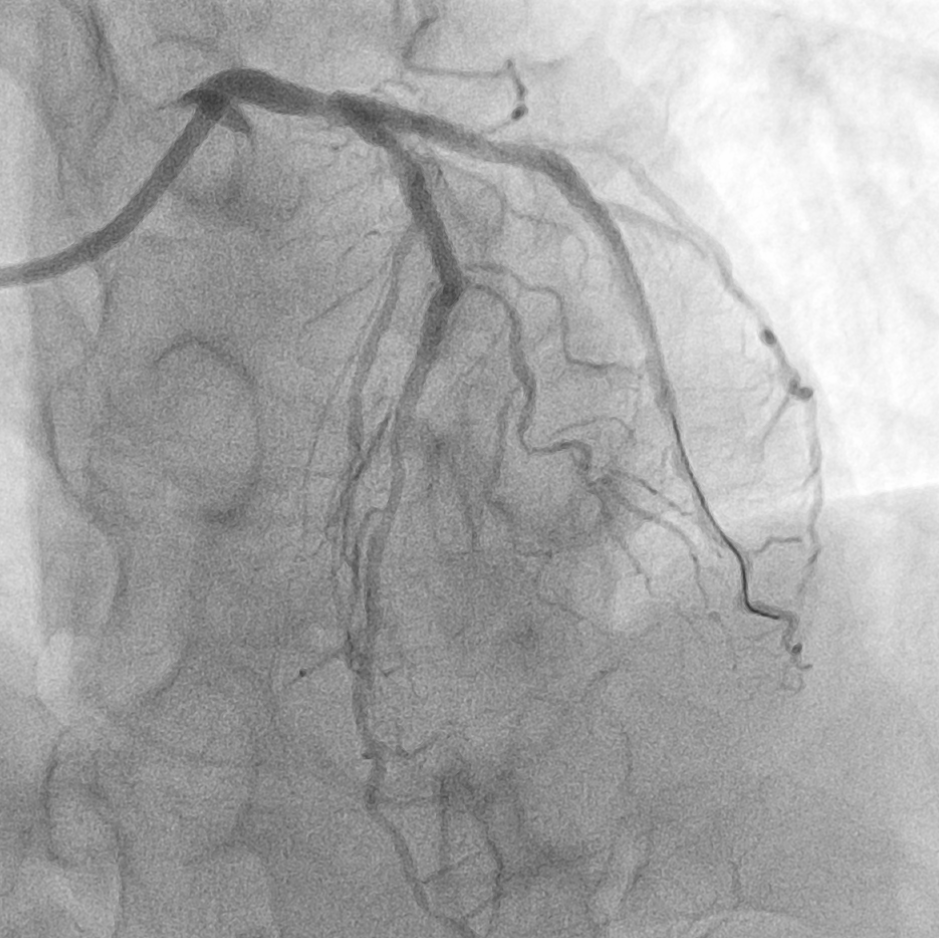

用时约40分钟,在患者无明显不适的情况下顺利完成介入治疗。术后患者顺利转入病房,并计划于近日出院。

Shockwave球囊冲击波治疗后,顺利植入支架

LCX术后QFR值为0.86